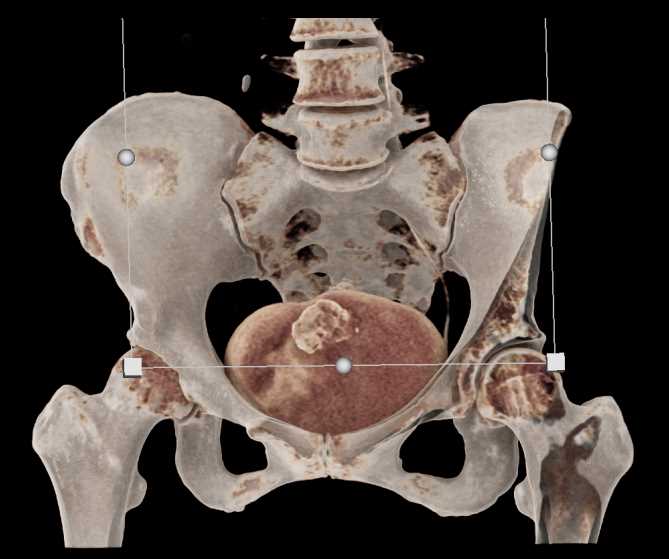

Urachal Carcinoma of the Bladder